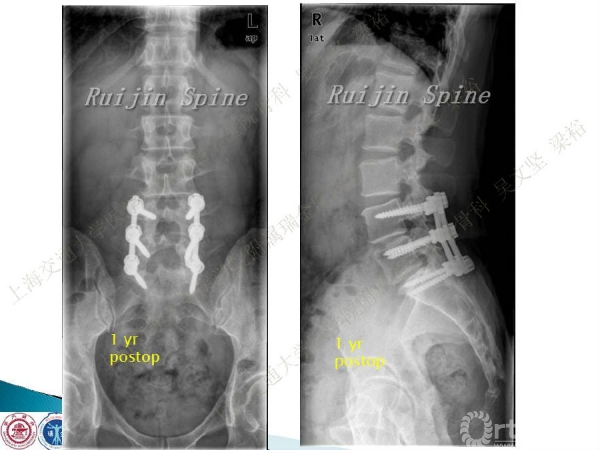

腰椎融合术后临近节段发生的退行性病变(adjacent segment disease,ASD))是一种常见的并发症。ASD的发病率相当高,而且涉及的范围很广。传统翻修手术治疗ASD有软组织剥离多、出血多、术后康复时间较长以及引起新的并发症的风险。本文结合病例介绍了运用Stand alone DLIF技术治疗ASD的方法与其优势。